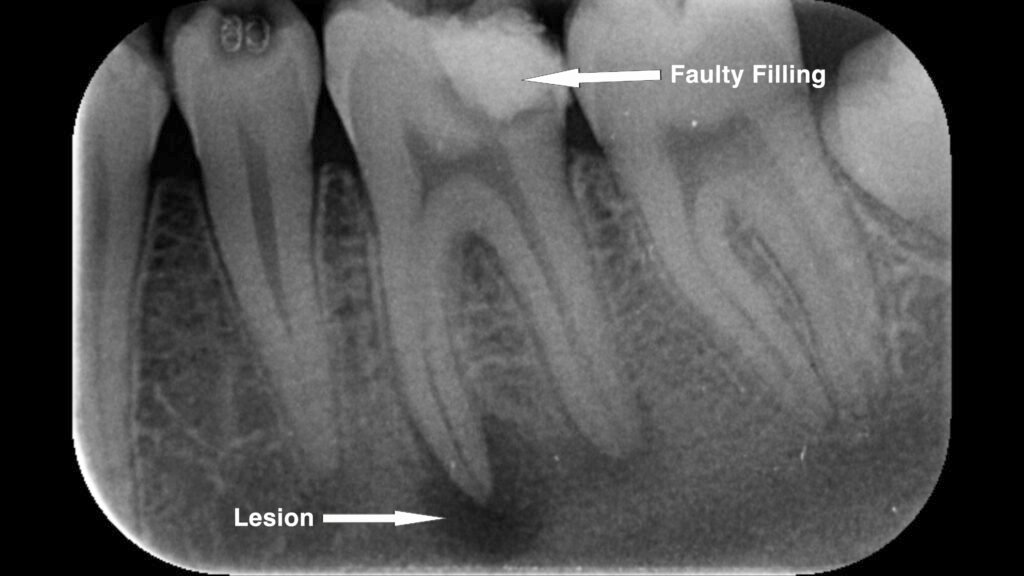

A similar problem can be seen in the case below, where a faulty filling led to the development of a periapical lesion at the root tip. This highlights how inadequate restorations can cause serious complications if the underlying issue is not properly addressed.

This case study presents the journey of a patient who came to me after experiencing pain from a faulty filling done by another dentist. The initial treatment was performed without proper examination and only addressed the surface issue for a low fee. As a result, the patient developed severe pain, tenderness, and a periapical infection at the root tip, putting the tooth at serious risk.

Upon examination and radiographic analysis, I found that the previous dentist had not properly diagnosed the underlying problem. The tooth was nearly lost due to the infection. The patient was very concerned and expressed a strong desire to save the tooth at any cost. I explained that the prognosis was poor, but I would use my best skills to try to save it.